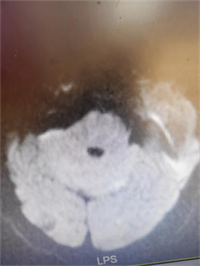

急诊科医师接诊时患者已中度昏迷,鼾式呼吸,小便失禁。立即完善急诊头颅CT提示左侧丘脑及侧脑室旁脑软化灶。头颅MRI提示小脑、两侧枕叶、左侧顶叶急性脑梗死。